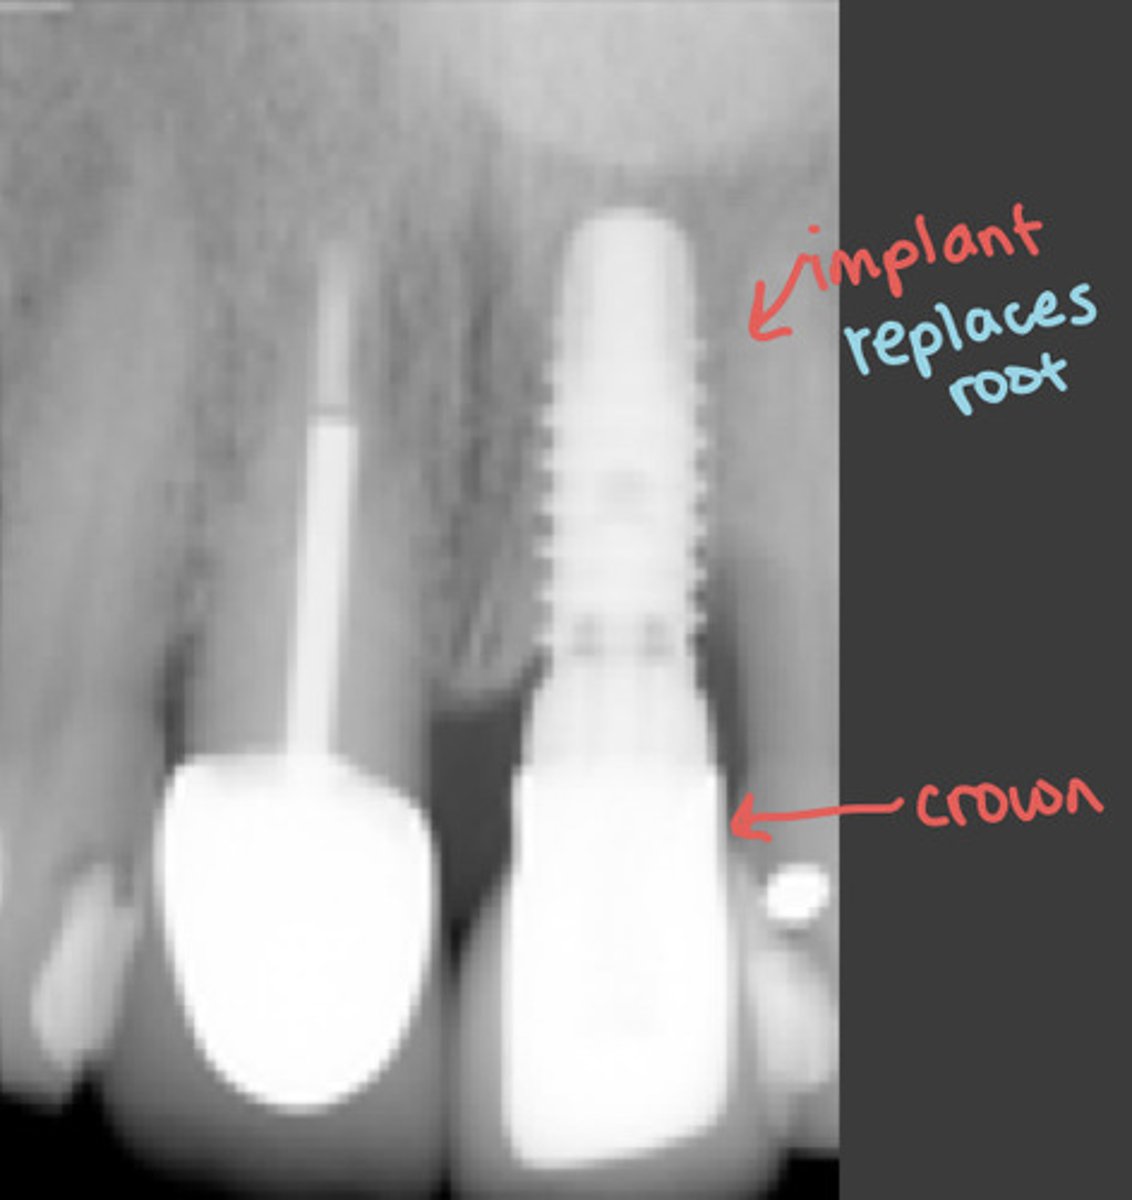

implants